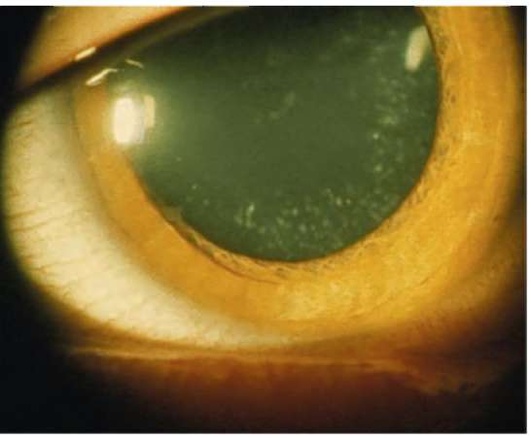

Рис. 33.5. Катаракта при сахарном диабете